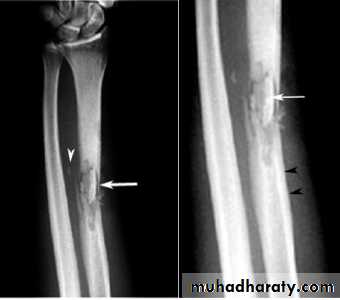

The initial radiographs are normal as bone changes are not visible until 10 -14 days after the onset of the infection.

the earliest sings on plain radiographs are soft tissue swelling , and bone destruction in the metaphysis with a periosteal reaction that eventually may become very extensive and surround the bone to form an involucrumpart of the original bone may die and form a separate dense fragment known as a sequestrum

a radionuclide bone scan will show increased activity both on the early ( blood pool ) images reflecting hyperaemia and on the delayed bone phase images.

U/S can demonstrate sub periosteal collections of pus .

MRI is the imaging modality of choice & shows evidence of bone odema and pus accumulation in the bone & soft tissue .distinction of neoplasm from osteomyelitis :